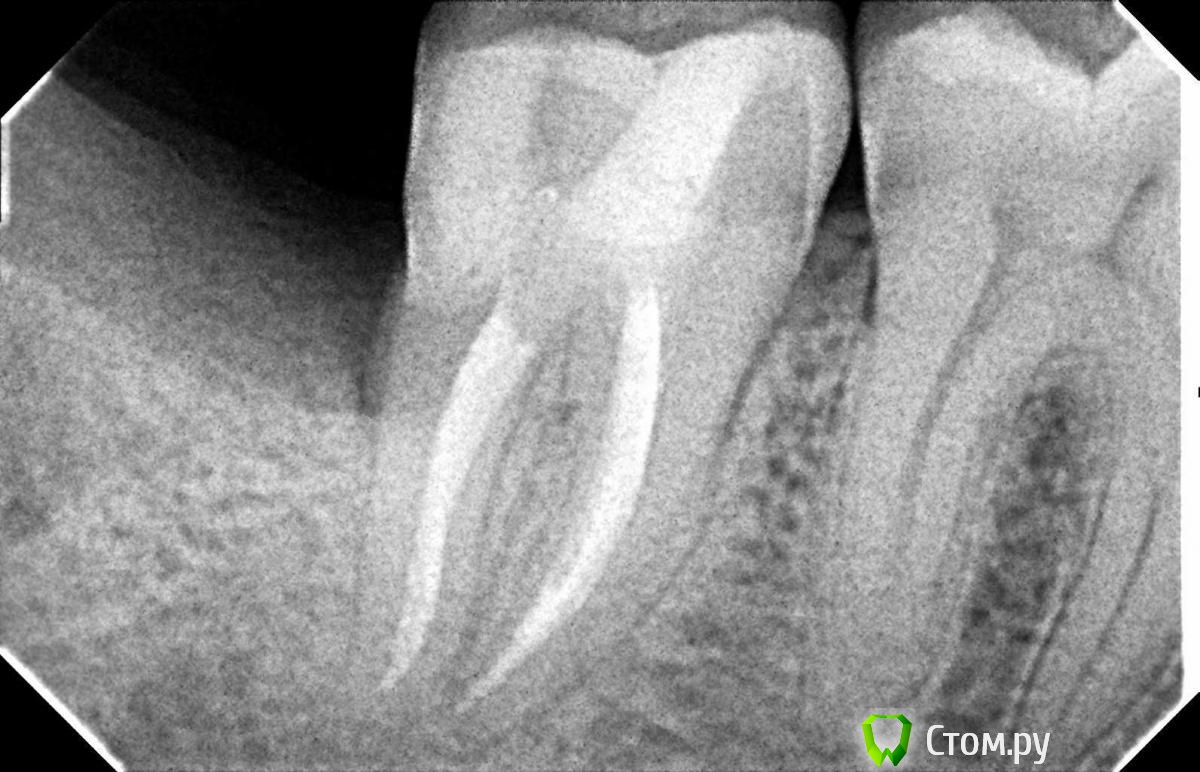

Hans85 Опубликовано 8 января, 2014 Поделиться Опубликовано 8 января, 2014 Только зарегистрировался на форуме,хотелось бы познакомится с коллегами.для начала выкладываю небольшой кейс с названием "Почти мини".Направлен пациент прошло 6 месяцев после фиксации композитной вкладки,заболел.Эндо без рук (только контроль проходимости 10 К-file)Rece+ProFile,пломбирование волна.Всем здравствуйте.P.S Сан Саныч привет)). 12 Ссылка на комментарий

Hans85 Опубликовано 8 января, 2014 Автор Поделиться Опубликовано 8 января, 2014 Привет. Тут ретрит? Логическую цепь картинок выстрой нормально... Первичное эндо Александр Александрович.VTVT техника обработки каналов. Ссылка на комментарий

Hans85 Опубликовано 8 января, 2014 Автор Поделиться Опубликовано 8 января, 2014 НУ еще чуток доступа может кому будет интересноПациент - геморная кариозная полость по дистальной поверхности 47,точка сообщения с полостью зуба обнаружилась,традиционный доступ уничтожил бы зуб,пришлось хитрить. 11 Ссылка на комментарий